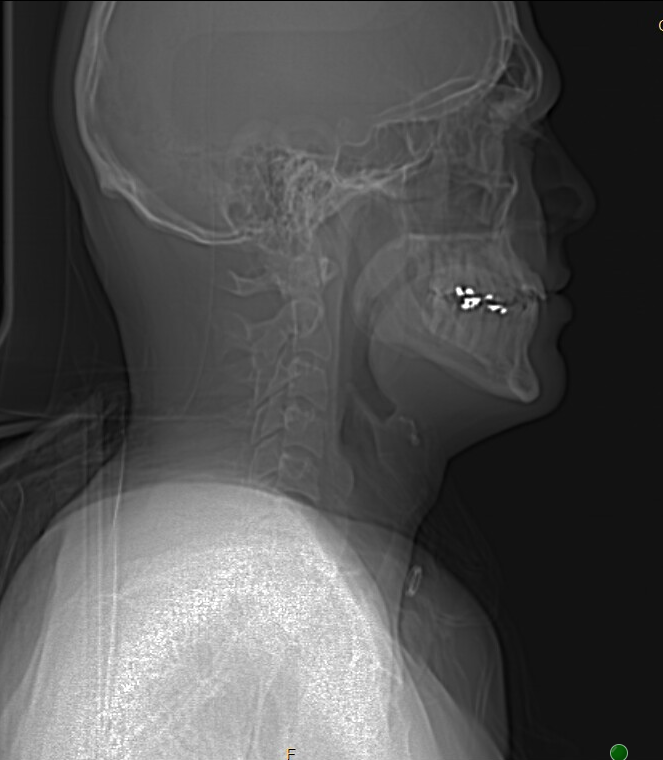

Not sure if any of these helps but I can try to get more. Here are some of my images

I checked the images they put under results and I don’t see any “axial views” can you show me what the axial view looks like? I pulled some more do these help?

This is the “sagittal” view you posted.

@Rfoxed - In your video images, I can see that your styloids are pretty normal length but are chunky. The left one has a “finger” of calcification at its tip & the right one may too. These features of thickness & irregular shape could predispose them to be causing some of your symptoms. The transverse processes of your C1 may be more rotated posteriorly than normal but that is likely an incidental finding that is of no significance.

Your hyoid bone looks ok to me, but as @TML said, w/o being able to see the local veins & arteries, it’s impossible to tell if it may be contributing to your symptoms.

Other things of note are that you have an excess bony growth on the left side of C1 as well as an atypical shape to the spinous process of C2. I don’t know if either of these could be contributing to your symptoms. I just wanted to point them out.

Your cervical spine has mostly lost its lordotic curve which brings your styloid & hyoid bone into closer contact w/ nerves, veins & arteries in your neck. That can be corrected with gentle exercises. (see this discussion: List of my favourite resources on YouTube to learn anatomy)

I suspect my findings aren’t going to be instrumental in you getting a proper diagnosis but they are points of interest perhaps for a discussion w/ Dr. Cognetti.